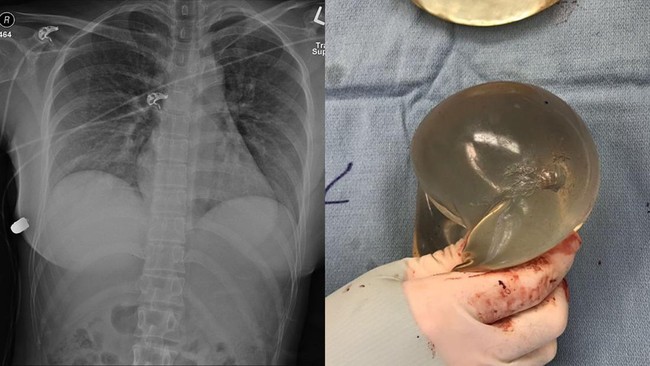

Tembakan implan payudara (Foto: Sage Journals)

Seorang wanita selamat dari tembakan misterius setelah peluru yang menghujamnya, tersangkut di implan payudara silikon miliknya.

Tembakan itu tepat mengenai bagian atas putingnya. Beruntungnya, peluru tidak menembus organ vitalnya, melainkan tertahan di payudara implan berukuran 450 ml.

Setelahnya, wanita itu dipindahkan ke pusat trauma untuk menjalani operasi. Dokter harus mengangkat implan kedua payudaranya. Dokter menemukan saluran peluru tepat di bawah luka masuk hingga payudara kanan.

"Berdasarkan lintasan peluru masuk secara klinis dan evaluasi radiologis, satu-satunya sumber defleksi peluru dari peluru adalah implan payudara kiri. Implan ini melapisi jantung dan rongga intratoraks dan karena itu kemungkinan besar menyelamatkan nyawa wanita tersebut," tulis laporan tersebut yang dikutip dari People.